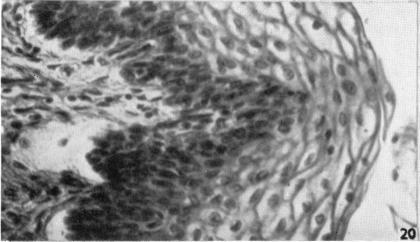

The development of the human vagina.

J Anat. 1957 Oct;91(4):490-509.